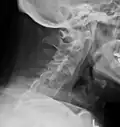

Lateral X-ray of the neck in ankylosing spondylitis -